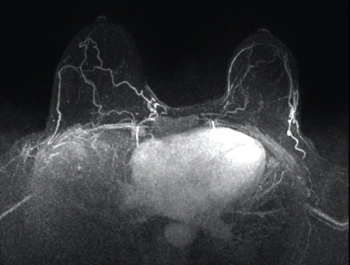

The value of GBCA in MRI images

Author(s)Ilana Cass, MD, Rola Saouaf, MD

These ten images can help ob/gyns recognize the additional information GBCA administration provides in MRIs.